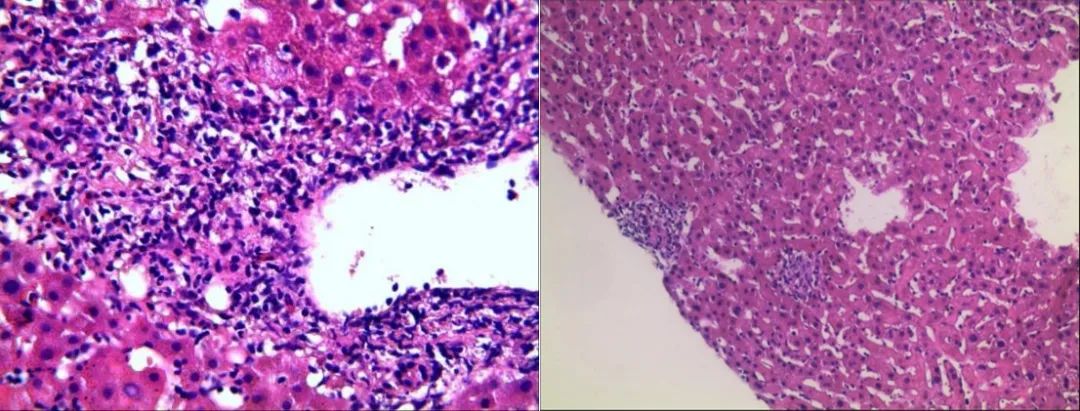

2022-11-21行肝穿活检:肝组织结构大致正常,未见淤胆及脂变,肝实质散在点状坏死灶及慢性小肉芽肿结节分布;全切片查见5个较为完整的汇管区,小胆管轻度扩张,数目不增加,管周较多淋巴细胞、浆细胞及少量中性粒细胞浸润,侵蚀界面,个别汇管区组织细胞聚集、小肉芽肿形成。考虑特发性肉芽肿性肝炎。免疫标记:CD34(灶+)、CK19(小胆管+)、HbsAg(-)(图2)。

图2. 行右肝穿刺,肝组织结构大致正常,未见淤胆及脂变,肝实质散在点状坏死灶及慢性小肉芽肿结节分布;全切片查见5个较为完整的汇管区,小胆管轻度扩张,数目不增加,管周较多淋巴细胞、浆细胞及少量中性粒细胞浸润,侵蚀界面,个别汇管区组织细胞聚集、小肉芽肿形成。

该患者肝酶表现为ALP、γ-GT明显升高,而ALT、AST轻度升高,且梅毒血清学实验阳性,肝炎病原学、自身免疫性肝炎抗体等检查全阴性;肝脏病理示:小胆管轻度扩张,数目不增加,管周较多淋巴细胞、浆细胞及少量中性粒细胞浸润,侵蚀界面,个别汇管区组织细胞聚集、小肉芽肿形成。因此在排除药物、自身免疫等其他可能原因,该患者考虑梅毒感染导致肝损害可能性大。

梅毒性肝炎是一种罕见的疾病,患者一般没有特定的症状,升高的肝酶,尤其是碱性磷酸酶和γ-谷氨酰转移酶作为特征之一,其组织学特征包括胆管炎症浸润和肉芽肿性改变,这可能引起血液中碱性磷酸酶和GGT水平升高有关;且常在疾病的第二阶段才会被发现。成人梅毒性肝炎的临床表现往往是非特异性的,临床上早期梅毒性肝炎极易漏诊、误诊,常见的肝脏损伤表现有乏力、纳差、黄疸等[7]。梅毒皮疹通常表现为非瘙痒性多发性红斑和非连续性斑丘疹病变,好发在躯干、手掌和足底,其他常见症状包括低烧、腹痛、头痛、喉咙痛、头痛、体重减轻、关节痛或肌痛、脾肿大、淋巴结病和葡萄膜炎[1]。总之,在对于肝酶(主要是胆汁淤积酶)不明原因升高和不安全性暴露的流行病学背景的患者,应考虑这种病因,早发现早治疗。